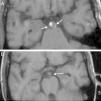

Arteriopatía aneurismática cerebral e infección por el virus de la inmunodeficiencia humana

Cerebral aneurysmal arteriopathy and human immunodeficiency virus infection